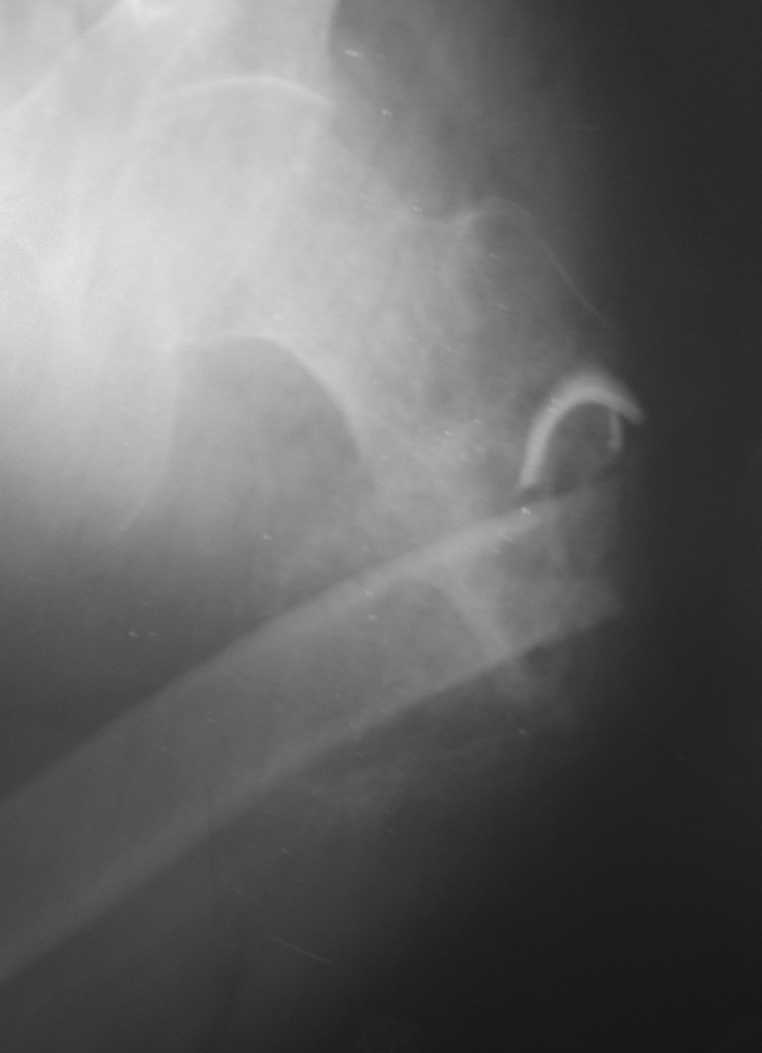

Уважаемые коллеги! Прошу помощи по приведенному случаю. Пациент 34 лет бомж получил травму окло 1,5-2 мес назад. За мед помощью не обращался. При поступлении левая нижняя конечность резко ротирована кнутри, варусная деформация бедра. По наружной поверхности рана 2 на 2 см с незначительным серозно гнойным отделяемым,умеренными грануляциями, в ране дистальный отломок бедреной кости. Патологическая подвижность в области перелома назначительная. Проведена попытка репозии дистракционным аппаратом, с незначительным эффектом (несколько уменьшилась внутренняя ротация.Что делать дальше? Остеотомия? Санация гнойного очага

Я бы начал с резекции мёртвой кости и хирургической обработки раны, поставил бы АВФ и цементные бусы с антибиотиками. После 6-ти недельного курса антибиотиков, фиксировал бы перелом штырём. Так как перелом весьма проксимальный (трудно судить по этому рентгену, надо сделать рентген с бедром на вытяжении), то есть вариант резекции прохимального отломка (Girdlestone arthroplasty). Нога укоротиться и пациент будет хромать, но будет ходить без болей. Но его можно будет мобилизировать довольно быстро, избегая проблемы с длительным постельным режимом и вытяжением. Учитывая, что больной вероятно не будет особо строго следовать указаниям врачей, это неплохой вариант для него и избежит осложнений с длительным лечением.

Произведена секвестрэктомия, остеотомия костной мозоли(кстати говоря мозоль оказалась довольно таки приличной) Рана ушита нагрухо. Наложено ДСВ за мышелки бедра. Рана зажила первичным натяжением. Пациенту наложен коксит, готовится на выписку.